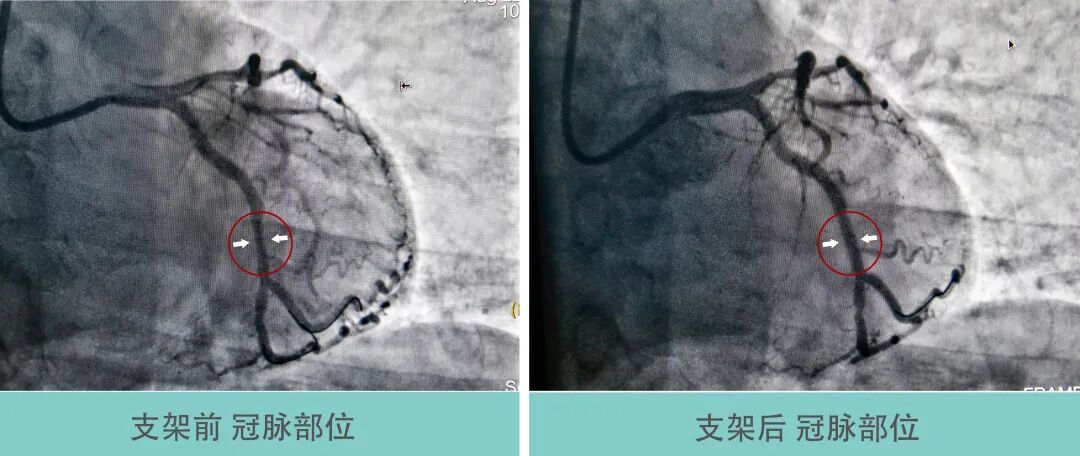

经与患者家属沟通,决定对病变明显的回旋支行PCI术,对其他病变血管暂时行内科药物保守治疗。术中应用导丝分别送至回旋支远端及钝缘支远端,应用球囊预扩张后造影显示病变血管狭窄改善不明显,遂给予支架一枚释放于回旋支中段至钝缘支开口,血管狭窄得到显著改善,手术顺利,病人术中无不适,拔除鞘管局部加压包扎,患者安返病房。